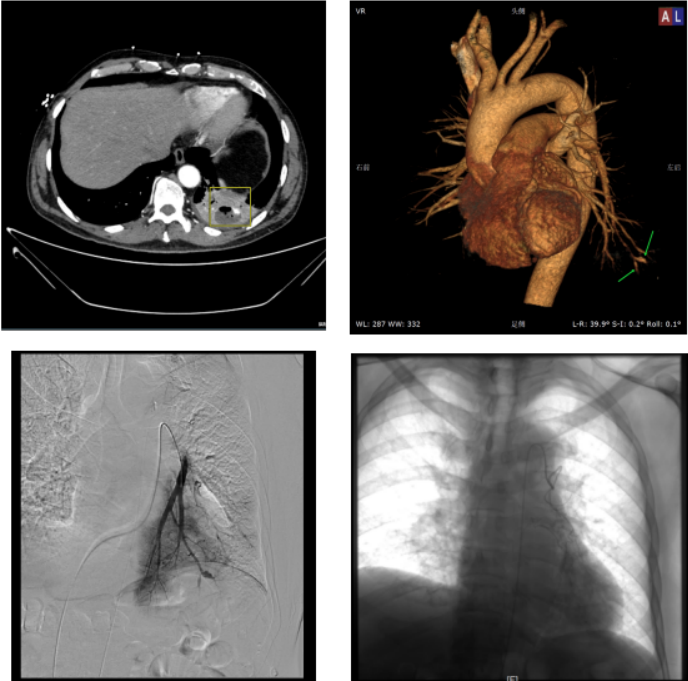

获得性PAPs的常⻅原因是创伤(通常为医源性)、感染、⾎管炎(特别是⽩塞病)和肿瘤。2017年发表的一篇文献纳入了24例患者,分析发现导致这些患者出现PAPs的主要原因包括感染、创伤、肿瘤、肺栓塞、支气管扩张、肺纤维化及特发性原因[4]。图源:AJR Am J Roentgenol, 2017, 208(1):84-91.从CT来看,PAPs可以分为中央型和外周型两种。中央型PAPs位于肺动脉干,定义肺动脉干直径29 mm或右叶间动脉直径17 mm,它们常与肺动脉高压有关。外周型PAPs位于肺内动脉上,很容易遗漏。由于急诊大咯血通常会行CT增强检查,然后再行支气管动脉栓塞,尤其在急诊情况下,可能会遗漏PAPs,进而出现危及生命的大咯血。越是远端血管越容易出现此种情况,因为远端血管壁较薄,而且被破坏。图源:Br J Radiol, 2017, 90(1073):20160783.图为一例53岁男性患者,因Swan-Ganz导管术诱发肺动脉假性动脉瘤(PAP):轴向CT血管成像(a,c),冠状重建(b)和三维重建(d)显示左上叶心尖段PAP(箭头)。患者接受保守治疗,病情稳定[5]。外周型PAPs造影分型:A型,肺动脉主干造影可见;B型,在肺动脉主干不可见,仅在选择性肺血管造影中可见;C型,支气管动脉造影可见,肺动脉造影不可见;D型,仅在肺CT血管造影可见,支气管动脉和肺动脉造影均不可见[6]。图源:Radiology, 2010 , 256(2):656-664.患者男性,70岁,入我院诊治,诊断为慢性阻塞性肺疾病(慢阻肺)、左⾆叶肺脓肿并PAPs、糖尿病。突发⼤咯⾎,⽓管插管。经抢救暂时止血。CT增强扫描发现血管膨大,肺动脉造影在肺动脉主干处发现PAP。CT容积重建技术(VR)也可见肺动脉瘤,其与肺动脉沟通。放置弹簧圈后⽌⾎。由于年龄较大,基础情况不佳,且有糖尿病、慢阻肺等合并症,患者于止血后半年余因肠穿孔死亡。

患者男性,65岁,⻋祸、外伤后出现咯⾎13天,⼤咯⾎,肋骨骨折,胸部损伤,左肺下叶⽀⽓管扩张伴感染。于我院就诊。急诊CT血管成像和VR,可见肺动脉分支与PAP相通,但肺动脉主干造影未见PAP,将导管置于左下叶肺动脉,造影可见动脉瘤。予肺动脉放置弹簧圈,造影显示PAP消失,后⽌⾎。